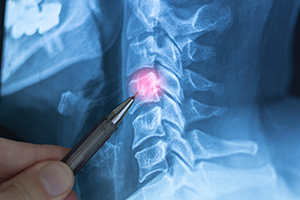

What a Spinal Disc Does and How Injuries HappenSpinal discs sit between the bones of your spine and act like shock absorbers. They help cushion movement and allow your back and neck to bend and rotate. When a disc is injured, it can lose that cushioning effect, bulge outward, or tear, leading to inflammation and pressure on nearby nerves.

Your imaging and exam findings help clarify which type you have, but your symptoms and your response to treatment are often what drive the real-world impact.

How Disc Injuries Are Diagnosed and DocumentedDisc injuries often require more than an X-ray. X-rays can help rule out fractures, but they do not show disc material or many nerve-related issues. Doctors often start with a physical exam that tests strength, reflexes, sensation, and range of motion. The notes from that exam can help show whether nerve involvement exists.

MRI imaging is commonly used to evaluate discs because it can show bulges, herniations, and signs of nerve compression. Your providers may also consider other tests if symptoms persist or if treatment is not working as expected.